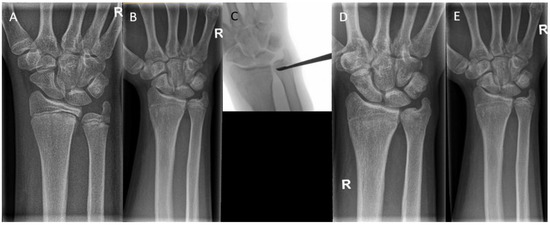

Figure 9. (A) A 17-year-old boy with a traumatic premature closure of the distal radial physis. (B) A closed radial physis, accompanied by an ulna plus. (C) Intraoperative radiographs during correction osteotomy of the radius combined with an epiphysiodesis of the ulna. (D) Radiographs six weeks postoperatively.

6.5. Osteotomy

In severe deformities or in cases with too little growth remaining, a corrective osteotomy can be performed in addition to or without epiphysiodesis to correct the length and restore the anatomical alignment (Figure 9). In the forearm, performing a dome or wedge osteotomy allows for an accurate correction of alignment and restoration of the axial length, but it is an invasive procedure with a longer recovery time than epiphysiodesis. Patients with a cubitus varus may need a rotational correction in addition to angular correction. In these cases, either a dome osteotomy or a closed lateral wedge osteotomy is a reliable and powerful method to achieve correction [25]. In isolated growth arrest of the radius, an ulnar shortening osteotomy may be needed to correct the ulnar overgrowth [63].